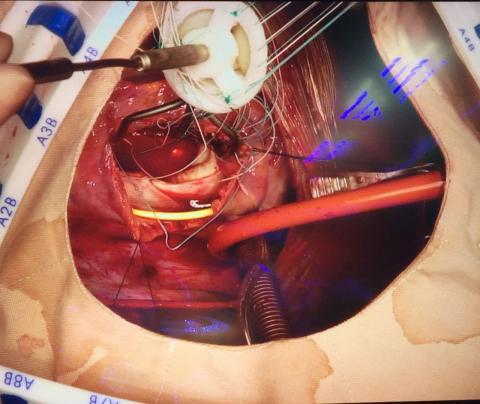

Valve repair/replacement

Yopie Afriandi Habibie was born in Lhokseumawe, April 23, 1980, completing his Bachelor's degree in Medical Faculty at Syiah Kuala University Banda Aceh (2005), Graduated as Medical Specialist Program 1 (Sp-1) Thoracic Cardiac & Vascular Surgery at the Medical Faculty of Indonesia University, in 2012. In 2005-2006 he served as a General Practitioner at RS. Hope Mother, Banda Aceh and General Practitioner in Refugee's Camp, Lhokseumawe. In 2013 he also attended an additional education as Junior Consultant on the Overseas Adult Cardiac Surgery Fellowship program at Narayana Health Institute of Cardiac Science's in Bangalore INDIA. In 2014 received a Fellow of Indonesian Heart Association (FIHA) from PERKI. Since 2018 Engaged with American College of Surgeon (ACS) and International College of Surgeon (ICS) as Fellowship (FICS and FACS). Currently, serving as Lecturer and Medical Staff Surgery at General Hospital dr. Zainoel Abidin, as Head of Cardiac Surgery and Vice Chairman of Integrated Heart Center of RSUDZA. Engage actively in various organizations of the European Cardiothoracic Surgery profession (EACTS), Asia (ASCVTS & ATCSA), American (STS), World Society for Pediatric & Congenital Heart Surgery (WSPCHS) and American Collage of Surgeon (ACS). From 2006 up to now he is appointed as a permanent lecturer at the Medical Faculty of Syiah Kuala University.

- Valve disease